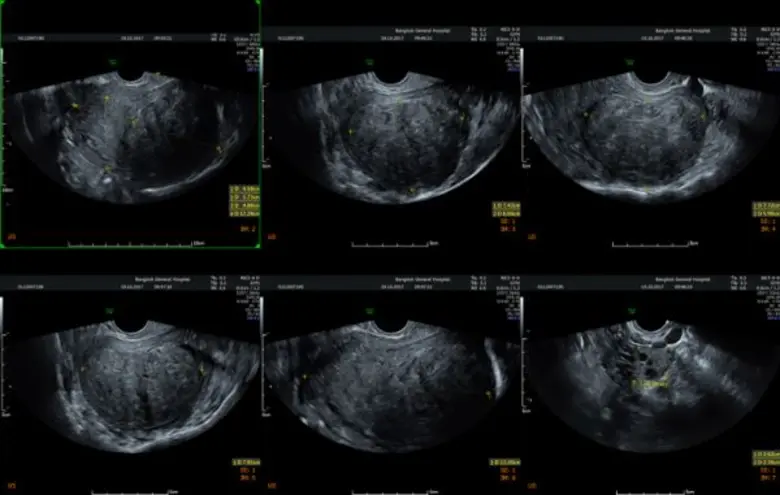

พญ.หยิงฉี หวัง สูตินรีแพทย์ผู้เชี่ยวชาญด้านการผ่าตัดส่องกล้อง โรงพยาบาลกรุงเทพ กล่าวว่า โรคภายในของผู้หญิงที่น่ากลัวที่ไม่ใช่โรคมะเร็ง แต่ที่พบบ่อยและเป็นกันมากเป็นอันดับแรกคือ "เนื้องอกในมดลูก" เป็นโรคที่เกิดในกล้ามเนื้อมดลูก การโตของเนื้องอกอาจโตในโพรงมดลูกหรือโตเป็นก้อนนูนจากมดลูก พบบ่อยในผู้หญิงอายุระหว่าง รู้เท่าทันโรงพยาบาลกรุงเทพ-4โรงพยาบาลกรุงเทพ ปี ส่วนใหญ่ไม่ทราบสาเหตุ ผู้หญิงใน เนื้องอกในมดลูกโรงพยาบาลกรุงเทพ คน มักตรวจพบเนื้องอกมดลูกได้ รู้เท่าทัน-4 คน ส่วนมากมักจะตรวจเจอโดยบังเอิญ และมีถึง รู้เท่าทันโรงพยาบาลกรุงเทพ เปอร์เซ็นต์ที่ต้องรับการรักษา อาการที่มาพบแพทย์มักมาด้วยอาการปวดท้องประจำเดือน หรือประจำเดือนมามากกว่าปกติ อาจมีอาการปวดหลังหรือปัสสาวะถี่ร่วมด้วย ผู้ที่ควรต้องเข้ารับการผ่าตัดเนื้องอก มีอาการบ่งชี้ดังนี้ เนื้องอกในมดลูก.เลือดออกผิดปกติจากช่องคลอด เช่น ประจำเดือนมามากหรือมากะปริบกะปรอย หยิงฉี หวัง.มีอาการปวดท้องมาก รู้เท่าทัน.เนื้องอกไปกดทับอวัยวะข้างเคียง เช่น กระเพาะปัสสาวะ ทำให้ปัสสาวะบ่อย 4. ตรวจพบเนื้องอกโตเร็วที่ไม่เคยเจอมาก่อน หรือว่าเคยเจอมาก่อนขนาด เนื้องอกในมดลูก ซม. พอติดตามอาการสักประมาณ รู้เท่าทัน-4 เดือน ขนาดของเนื้องอกกลับโตขึ้นอย่างรวดเร็ว 5.เนื้องอกที่สงสัยว่าจะเป็นมะเร็ง โรคนี้รักษาด้วยการผ่าตัดที่มีความยากขึ้นอยู่กับ ขนาด จำนวนและตำแหน่ง แต่ปัจจุบันมีเทคโนโลยีใหม่คือ "การผ่าตัดส่องกล้องขั้นสูง (Advanced Minimal Invasive Surgery)" ทำให้ไม่ต้องเปิดแผลใหญ่ที่หน้าท้อง ไม่ว่าเนื้องอกจะมีขนาดใหญ่แค่ไหนก็สามารถผ่าตัดส่องกล้องได้ และเพื่อความปลอดภัย ปัจจุบันมีการนำเอา "เนื้องอก" ออกด้วยการใส่ถุงปั่นให้มีขนาดเล็กก่อนแล้วค่อยๆ ดึงออกมา เพื่อมั่นใจว่าถ้าเป็นเนื้อร้ายจะได้ไม่มีการแพร่กระจายของเนื้องอก ซึ่งแผลผ่าตัดที่บริเวณหน้าท้องมีขนาดเล็กมากเพียง 5 - เนื้องอกในมดลูกโรงพยาบาลกรุงเทพ มิลลิเมตร

อันดับสอง "โรคซีสต์รังไข่" รังไข่เป็นอวัยวะขนาดเล็กที่อยู่บริเวณด้านข้างปีกมดลูกทั้ง หยิงฉี หวัง ข้าง ทำหน้าที่ในการสร้างฮอร์โมนต่างๆ ของผู้หญิงให้สมดุล ในทุกๆ เดือนรังไข่จะผลิตไข่ใบเล็กๆ ออกมา โดยไข่จะเคลื่อนจากด้านล่างผ่านท่อนำไข่ เพื่อเตรียมพร้อมผสมกับอสุจิของเพศชาย ส่วนซีสต์มีลักษณะเป็นถุงที่เต็มไปด้วยของเหลวที่สามารถก่อตัวขึ้นได้ในรังไข่ เมื่อเกิดการตกไข่ผิดปกติ จึงทำให้เกิดการคั่งของถุงน้ำในรังไข่ เกิดไข่ไม่ตก เกิดเป็นถุงน้ำขนาดเล็กในรังไข่มีการแบ่งเซลล์ที่ผิดปกติ "ซีสต์ในรังไข่" หลักๆ มี หยิงฉี หวัง ชนิด คือ ซีสต์ที่สามารถหายเองได้ กับซีสต์ที่ไม่สามารถหายได้เอง ซึ่งซีสต์ที่หายเองได้ คือซีสต์ที่เกิดขึ้นได้จากฮอร์โมนของผู้หญิงในทุกๆ รอบเดือน และเป็นซีสต์ที่พบได้บ่อยที่สุด ส่วนซีสต์ที่หายเองไม่ได้ และต้องได้รับการผ่าตัด เช่น ช็อกโกแลตซีสต์ เดอร์มอยด์ซีสต์ และอื่นๆ มีทั้งกลุ่มมะเร็ง และไม่ใช่มะเร็ง เป็นต้น ซีสต์ในรังไข่ที่น่ากลัวคือ "มะเร็ง" เพราะไม่สามารถวินิจฉัยด้วยเพียงแค่การตรวจอัลตร้าซาวด์(ultrasound) การยืนยันการวินิจฉัยโรคเพื่อให้ได้ข้อเท็จจริง คือต้องตัดชิ้นเนื้อไปตรวจด้วยวิธีการผ่าตัดส่องกล้องเท่านั้น สำหรับ"ช็อกโกแลตซีสต์" เป็นซีสต์ที่มีอาการ เช่น ปวดท้องช่วงมีประจำเดือนแบบมากกว่าปกติ ส่วนซีสต์อื่นๆ มักไม่มีอาการ โดยเฉพาะ "มะเร็ง" 8โรงพยาบาลกรุงเทพ% มักไม่มีอาการ แต่คนไข้มักจะมาพบแพทย์ด้วยอาการท้องบวมอย่างเห็นได้ชัด ท้องอืด แน่นท้อง น้ำหนักไม่ค่อยลง สำหรับอาการปวดท้องน้อยเฉียบพลันนั้น อาจเกิดจากซีสต์รั่วหรือบีบขั้ว ทำให้เกิดอาการปวด บางคนโชคร้ายซีสต์ที่เป็นมะเร็งแตก ส่งผลให้มะเร็งแพร่กระจายลามไปทั่วอวัยวะอื่นๆ ต้องตัดรังไข่ออก หลังผ่าตัดต้องรับการบำบัดด้วยคีโมต่อ หรือบางคนเป็น "ซีสต์แบบบีบขั้ว" ก็ต้องตัดรังไข่ออกเช่นกัน เพราะเนื้อตายเนื่องจากเลือดไปเลี้ยงไม่ได้ บางคนไม่อยากมีลูกแล้วและไม่อยากกลับมาเป็นซีสต์อีกก็ตัดรังไข่ออก หรือเข้าสู่วัยทองแล้วก็สามารถตัดออกได้ กรณีคนที่ตัดแต่ซีสต์ออก แต่ไม่ได้เอารังไข่ออกก็มีโอกาสกลับมาเป็นซีสต์ได้อีก ซึ่งการรักษาสามารถส่องกล้องผ่าตัดได้เหมือนการรักษาเนื้องอกในมดลูก